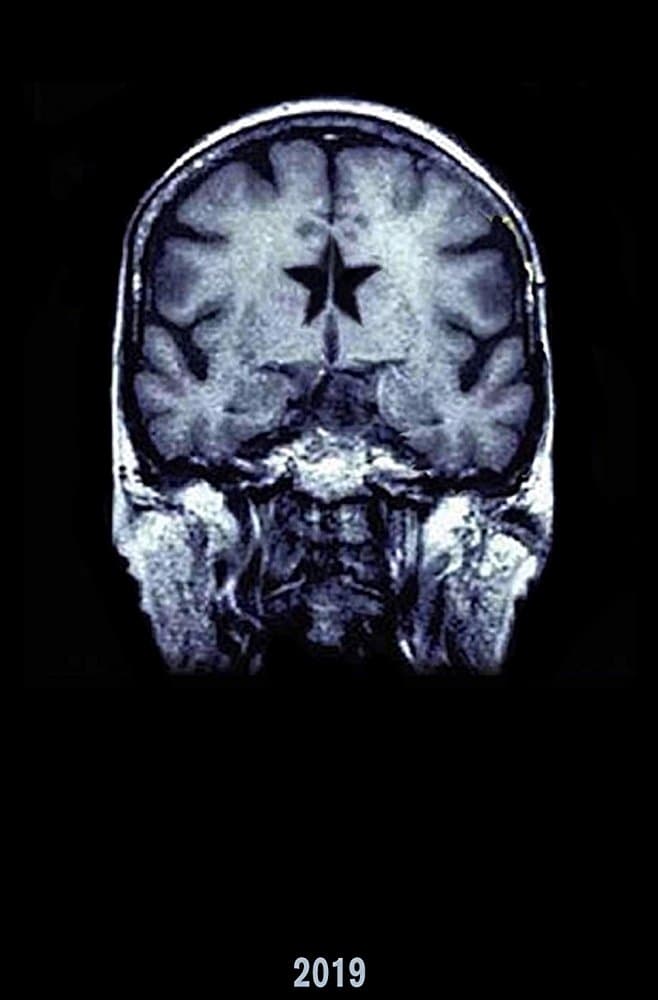

Grace is a robot incognito whose primary function is to represent humanity based on a generalization created from all social media and wireless communications. Rudy is her final test.